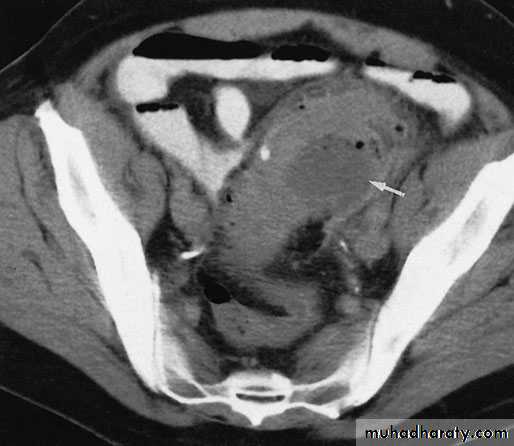

Diverticulosis, like 'irritable bowel' syndrome, is a diagnosis of exclusion, and symptoms should not be attributed to diverticulosis unless other diseases have been excluded by barium enema, sigmoidoscopy or colonoscopy. Although the diagnosis of acute diverticulitis is made on clinical grounds, it can be confirmed during the acute phase by (CT).

Computerized tomography scan showing a segment of thickened sigmoid colon with a paracolic abscess (arrow) in a patient with diverticulitis.

This will demon­strate not only the diverticula but also any associated pericolic abscess .Barium enemas & sigmoidoscopy are usually reserved for patients who have recovered from an attack of acute diverticulitis, for fear of causing perforation or peritonitis.